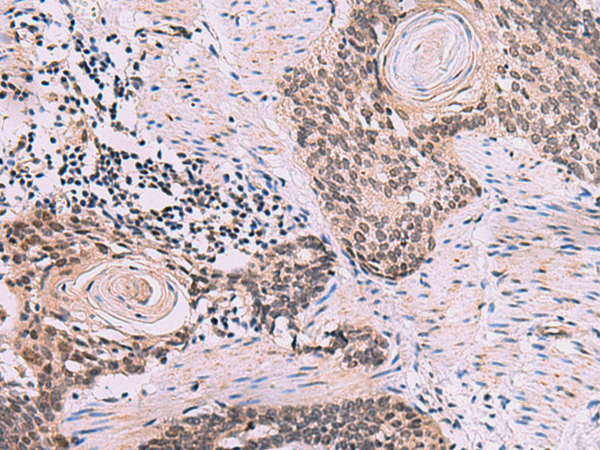

IHC positive control: |

Human esophagus cancer |

IHC Recommend dilution: |

50-300 |